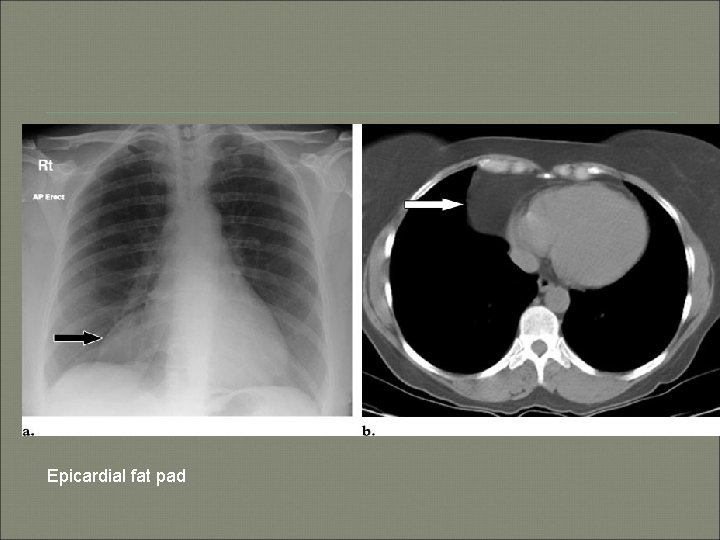

Epicardial fat pad